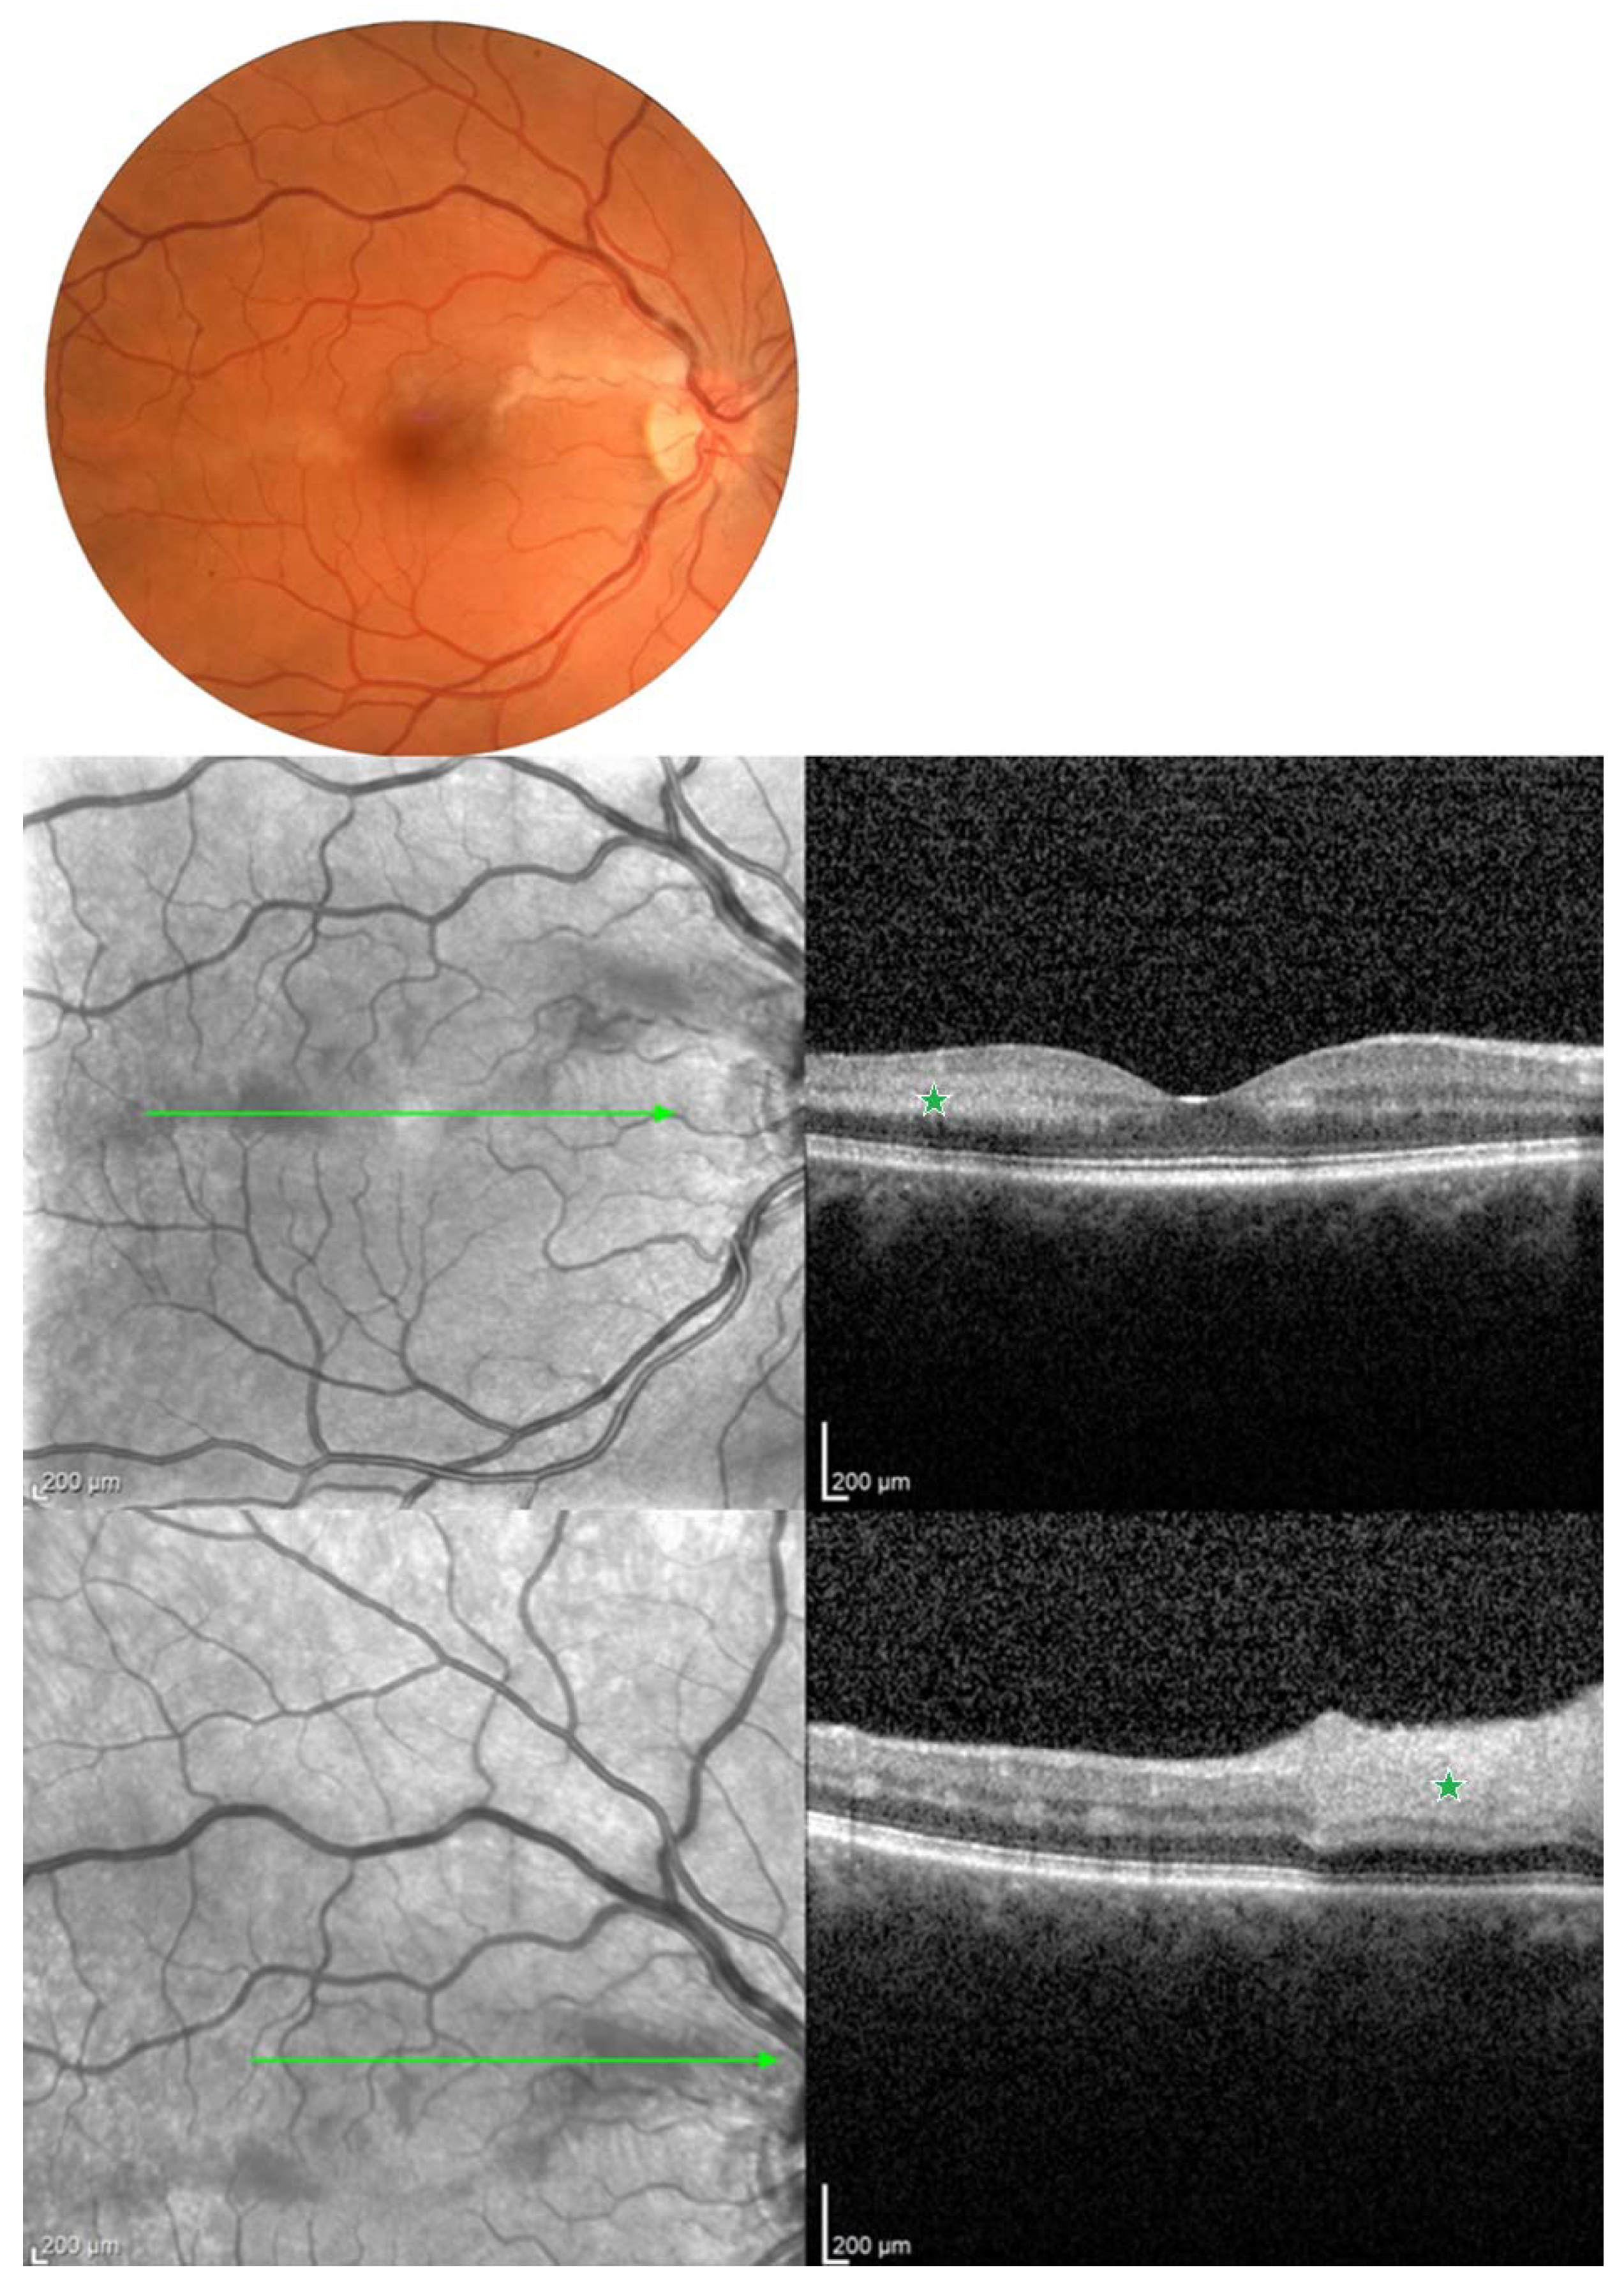

- Malerbi, F.K.; Novais, E.A.; Emmerson, B.; Bonomo, P.P.; Pereira, A.J.; Lottenberg, C.L.; Maia, A. Hyperbaric oxygen therapy for choroidal neovascularization: A pilot study. Undersea Hyperb. Med. 2015, 42, 125–131. [Google Scholar] [PubMed]